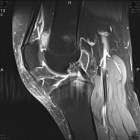

51 year old male with six month history of knee pain, worse after MVC

Zoom image: Radiological image Radiological image.